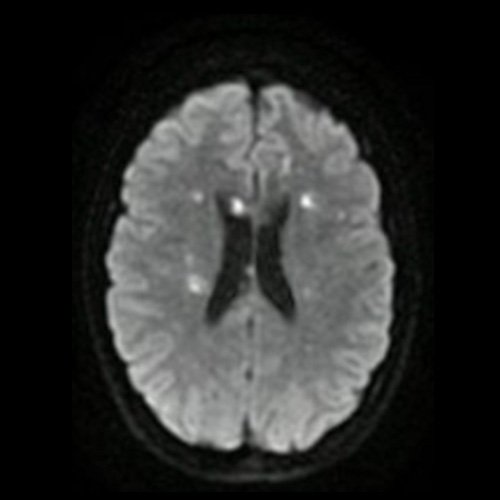

Día 2: RMI de cráneo (difusión – corte axial). Lesiones nodulares sólidas en sustancia blanca en centros semiovales y cuerpo calloso con restricción en difusión.

La RMI muestra lesiones hiperintensas en T2 y FLAIR a nivel periventricular y subcortical, incluido el cuerpo calloso y el centro semioval, así como en la sustancia gris, incluida la corteza, los ganglios basales y el tálamo. Las lesiones infratentoriales en el tronco encefálico, el cerebelo y la médula espinal son comunes. Suelen tener realce con gadolinio. Difusión restringida.